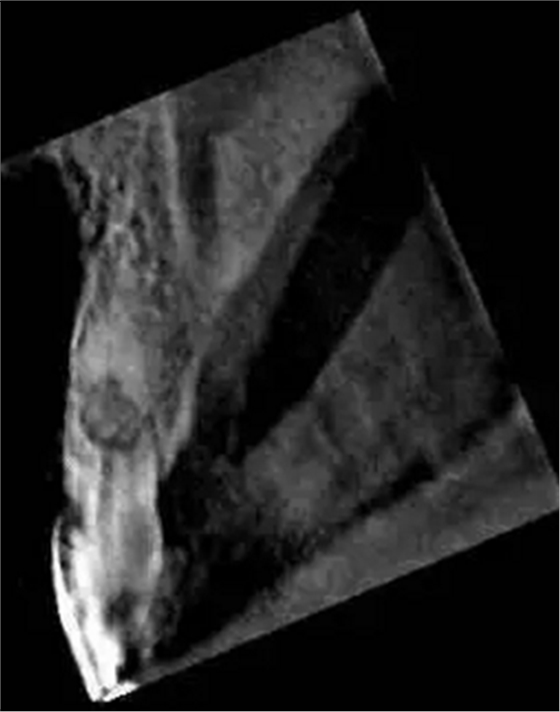

左上中切牙近遠(yuǎn)中有牙色充填體,邊緣繼發(fā)齲,牙齒不松動(dòng),輕微叩痛,患牙冷測遲鈍,牙齦未見異常。X線片示:充填體周圍繼發(fā)齲壞近髓,根中部大面積低密度影,蟲噬狀,內(nèi)部結(jié)構(gòu)顯示不清晰,根尖周未見異常。錐形束CT(CBCT)顯示根中部內(nèi)吸收多處可疑穿孔,缺損內(nèi)可見菜花狀鈣化物影像

近期研究和病例報(bào)告均顯示CBCT有助于牙根吸收病例的診斷[3, 6, 13]。本病例中使用CBCT判斷缺損大小、內(nèi)容物形狀和根管壁可能側(cè)穿孔的位置,起到了輔助診斷治療的作用。